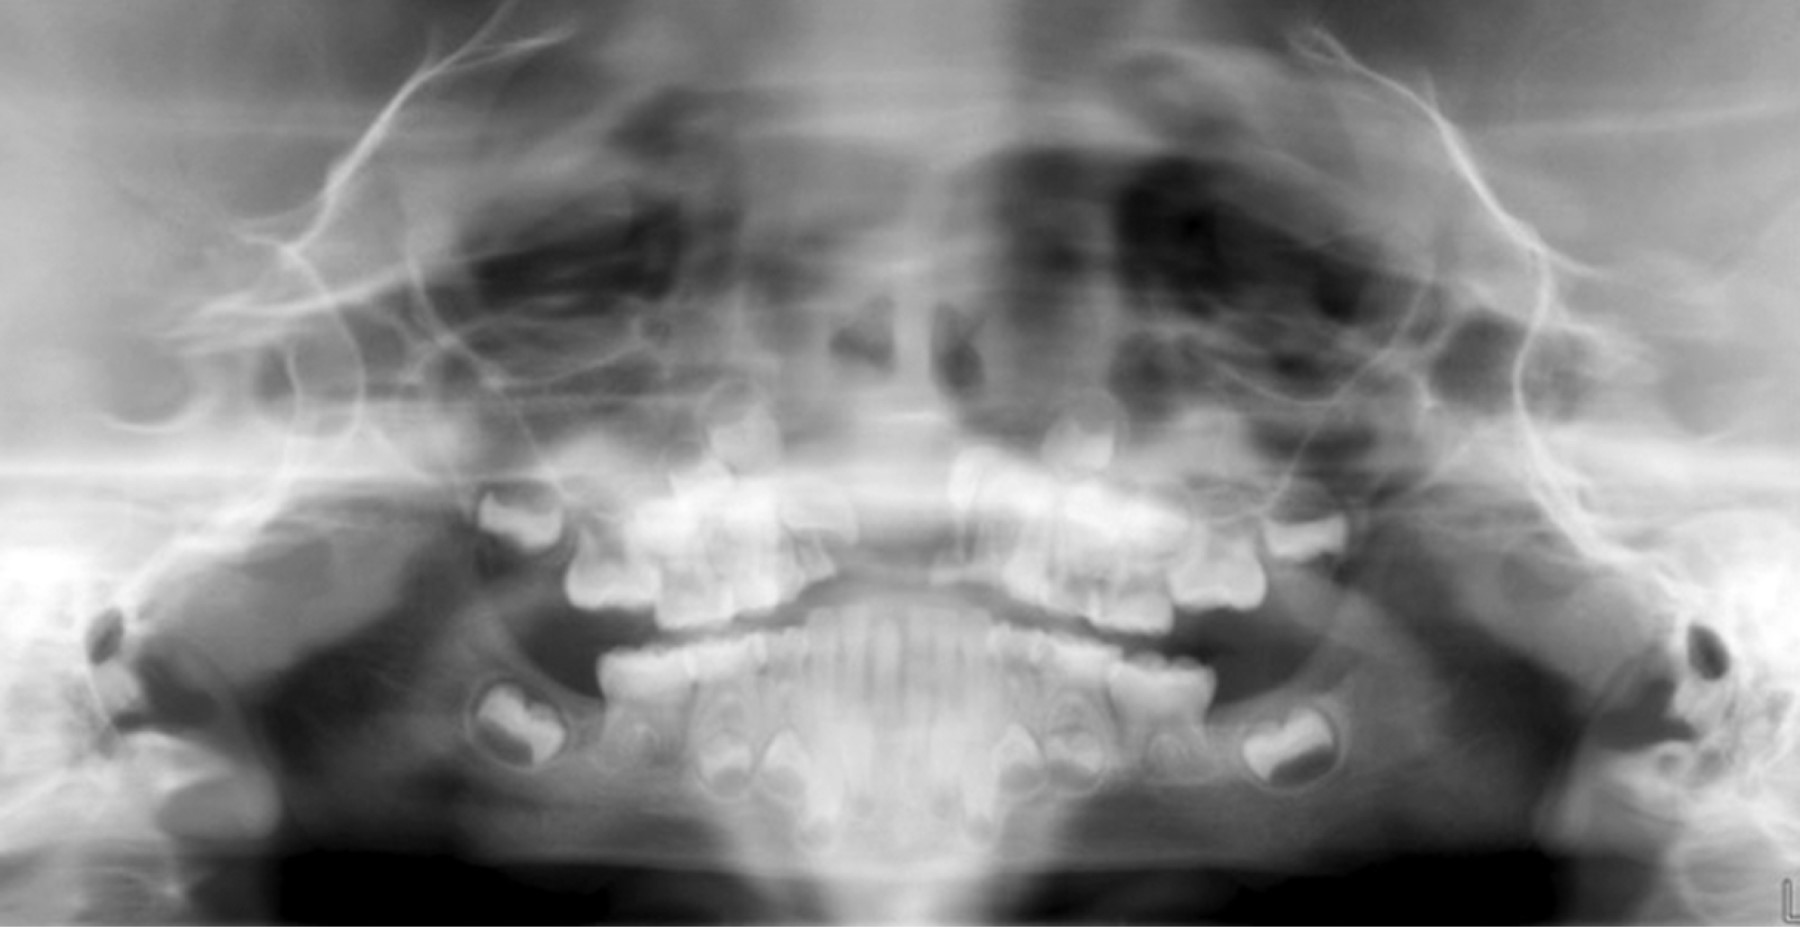

Radiográficamente, se observó un área unilocular amplia (Figura 3) que causaba desplazamiento dentario y de los gérmenes de incisivos centrales permanentes por su extensión hacia el piso de la cavidad nasal. La imagen computarizada Cone Beam permitió ver la presencia de una masa de 25 mm en la mayoría de sus dimensiones (Figura 4).

Figura 3